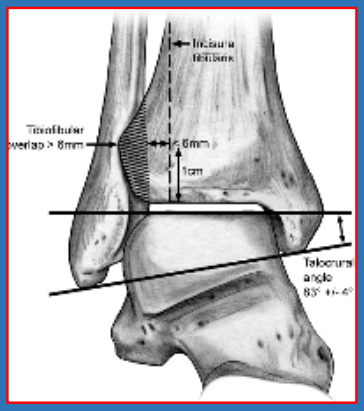

下胫腓联合分离

胫腓间隙、重叠,胫腓间隙在前后位上大于6mm或胫腓重叠在前后位上小于6mm、在踝穴位上小于1mm,即表示存在下胫腓联合的分离。

踝穴宽度 D线在距骨关节面下方5mm处,平 行于距骨关节面,与胫骨、腓骨相 交于a、b、c、d四个点 、踝穴宽度=ab-cd 、正常范围2~6mm。

在旋后外旋SER类型中:内踝间隙>4.5mm、骨折高度>7mm